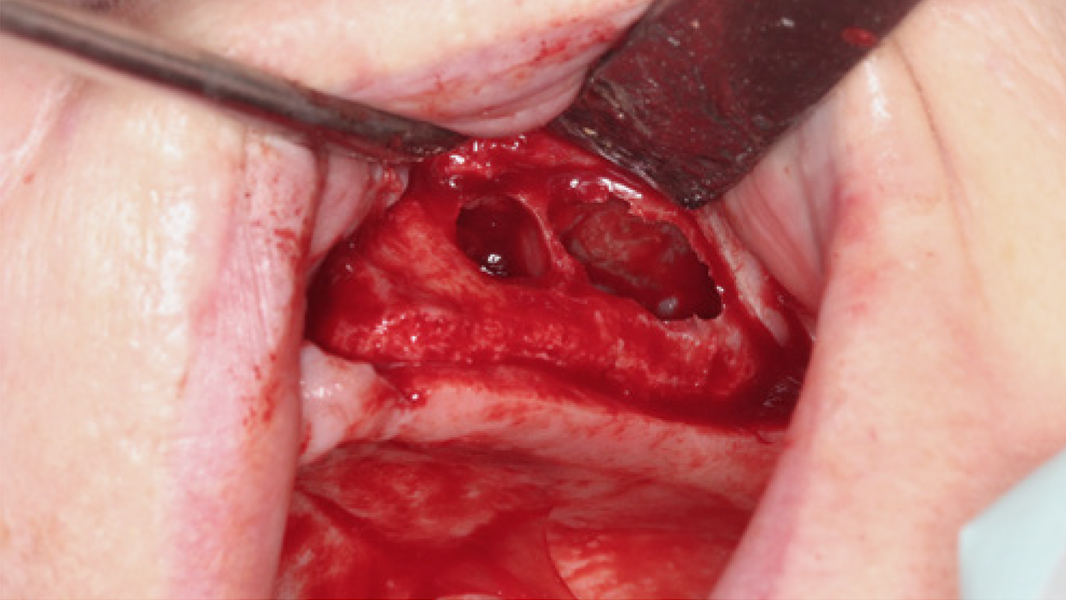

3 Kloss et al. Clin Case Rep. 2020, 8(5):886-893.

15 Data on File. Limited Market Release. Clinical Case Documentation.